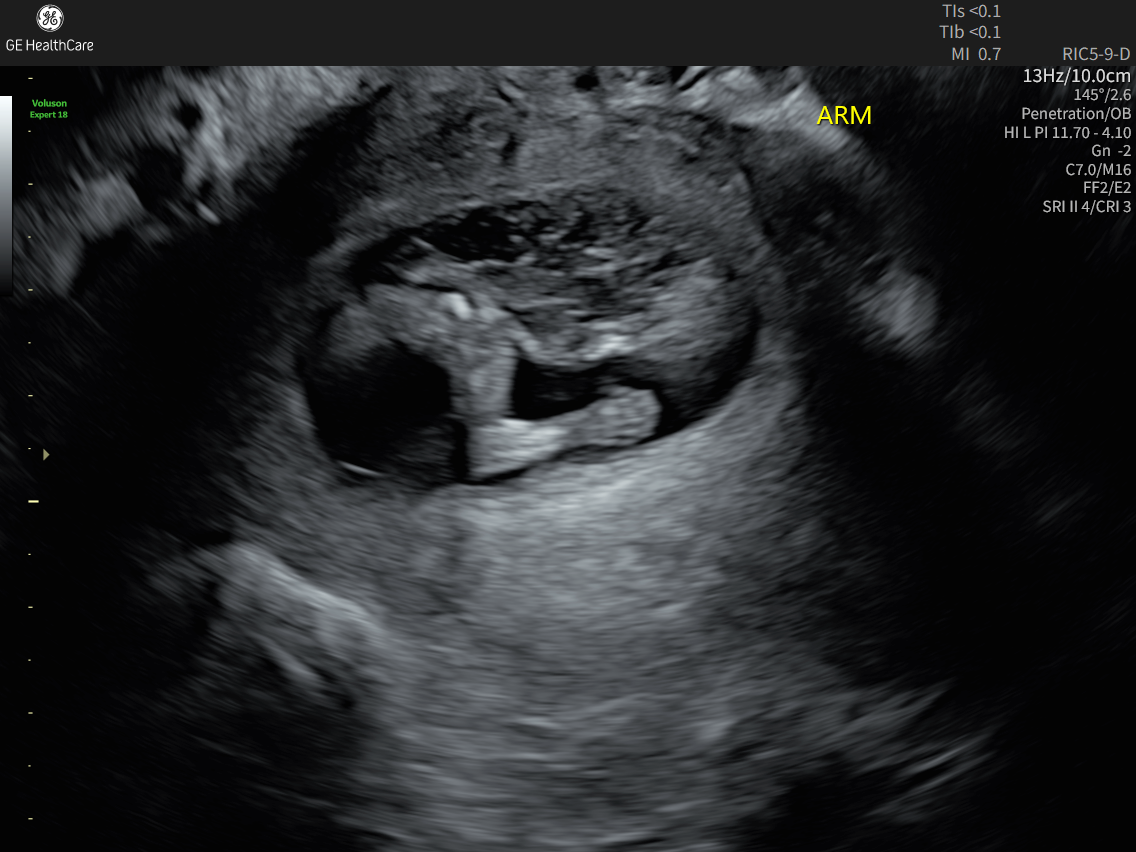

Me and my husband found out we were pregnant on November 2nd. We had an appointment with a high-risk doctor on December 22nd where a possible abdominal issue was found. We then went to our anatomy scan on February 2nd, and the abdominal issue they found at the previous appointment was worse than they originally anticipated. Our little girl was diagnosed with something called Limb-Body Wall Complex(LBWC). It basically means all of her internal organs are outside of her body, including part of her heart. It also can cause spinal issues, and her spine has a lot of curving that is not good. She’s basically twisted and curled up and “stuck” to the placenta wall to where she can’t really grow, and she’s measuring really small. It’s a fatal diagnosis and extremely rare. We have been going to weekly ultrasounds since for a weekly heartbeat check. Whenever we go in and there’s no heartbeat, we will go to labor and delivery and deliver her, unfortunately stillborn. There’s no known cause of this, nothing we did wrong, just a very sad and unfortunate circumstance. Any money donated will go to any hospital bills, time taken off work, a memorial service or cremation(whichever route we decide to go), Please keep us in your prayers over the next few weeks/months as we navigate this unimaginable and very tough time.❤️